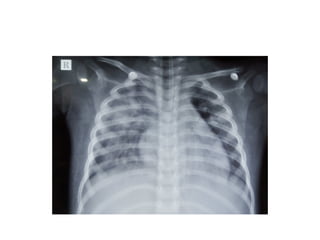

• Fever with cough and pulmonary infiltrates or community acquired

pneumonia.